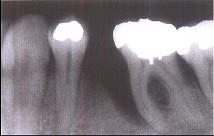

牙槽骨垂直型吸收的特点,除外 ( )

A牙槽骨不发生水平方向的吸收

B牙槽嵴高度降低不多,而牙根周围的骨吸收较多

C垂直吸收多形成骨下袋

D牙槽骨发生垂直或斜型方向的吸收

E与牙根面形成角型的骨缺损